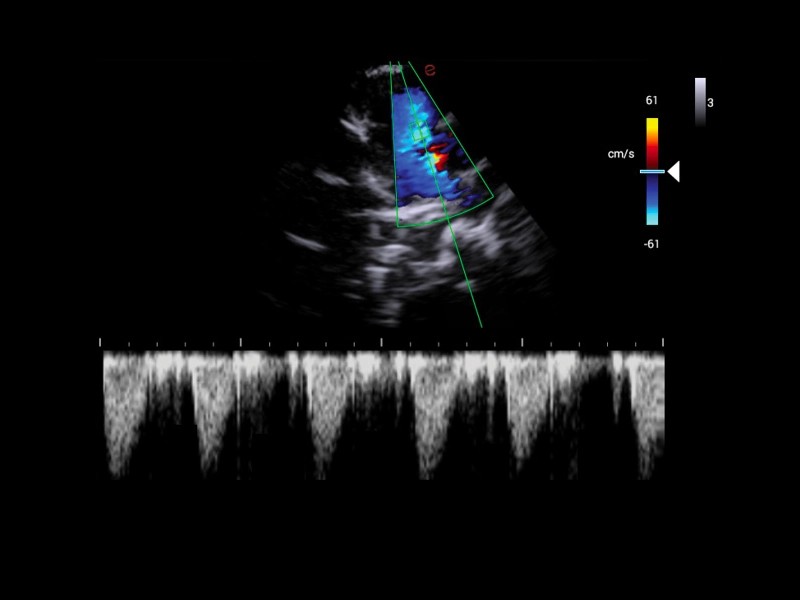

MyLab™X1 Go - Cardiovascular Doppler 02

MyLab™X1 Go - Cardiovascular Doppler 02